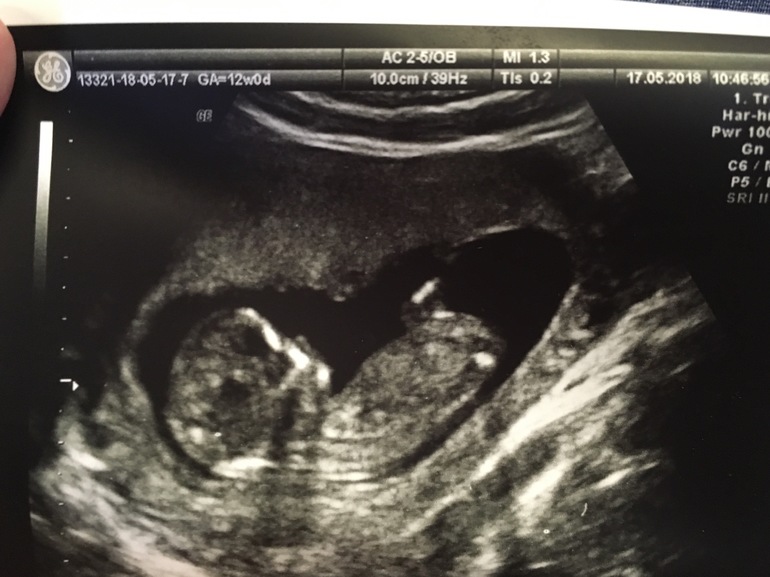

Первый скрининг

Вторая беременностьВ четверг сходили на первый скрининг. Как всегда волновалась, а вышла счастливая - счастливая. Записываю для истории :

КТР 61,3 мм

ТВП: 1,3

Малыш прикреплен по задней стенке. Говорят, похоже на девочку. Но я пока стараюсь об этом не думать. Узнаем через пару недель.

"Размер обуви " 10,03 мм)))

Опережает на 4 дня срок, все замечательно, никаких отклонений нет. Врач еле-еле смогла "поймать" и измерить ТВП, потому что ребёнок все время крутился, играл с ножками и ручками. И ротик так мило открывал. А когда папу позвали, сразу уснул)))

По крови тоже все отлично, все риски 1:100000